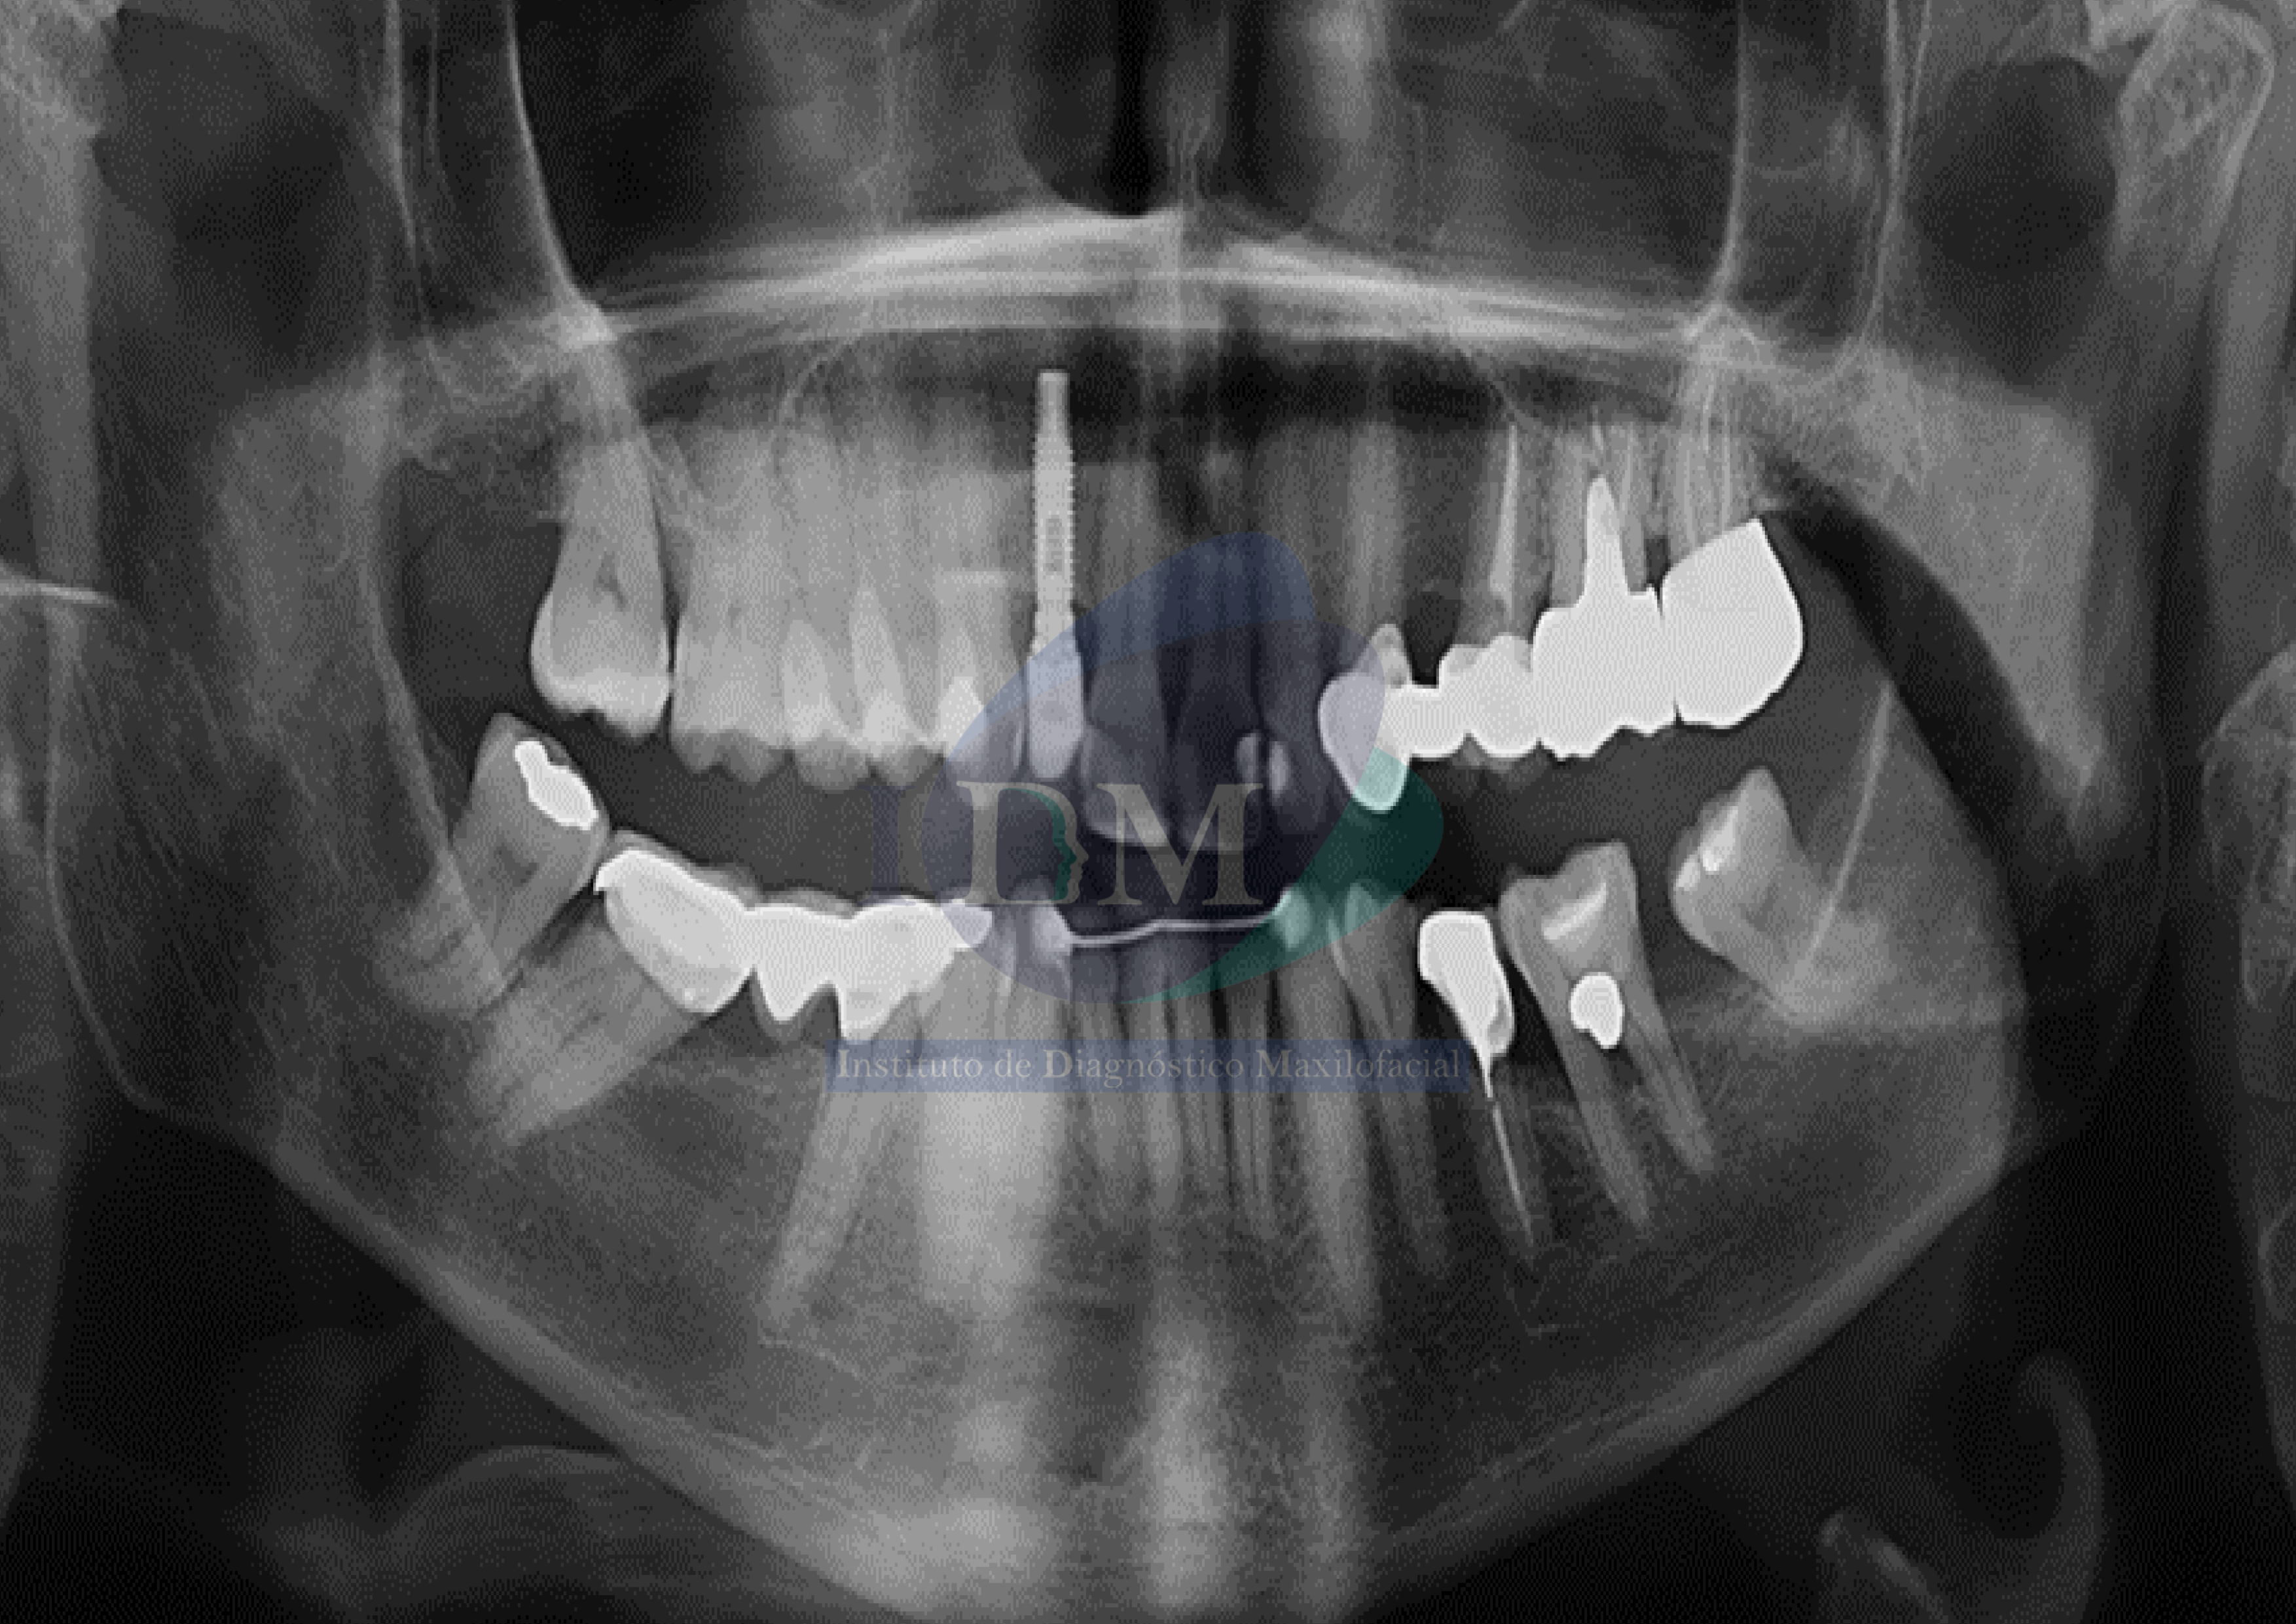

Paciente femenina de 66 años, es referida al Instituto de Diagnóstico Maxilofacial – IDM (Sede Surco) para evaluación integral.

En la radiografía panorámica se observan signos de aplanamiento del contorno de los cóndilos mandibulares y esclerosis del cóndilo mandibular izquierdo.

Radiografia Panorámica